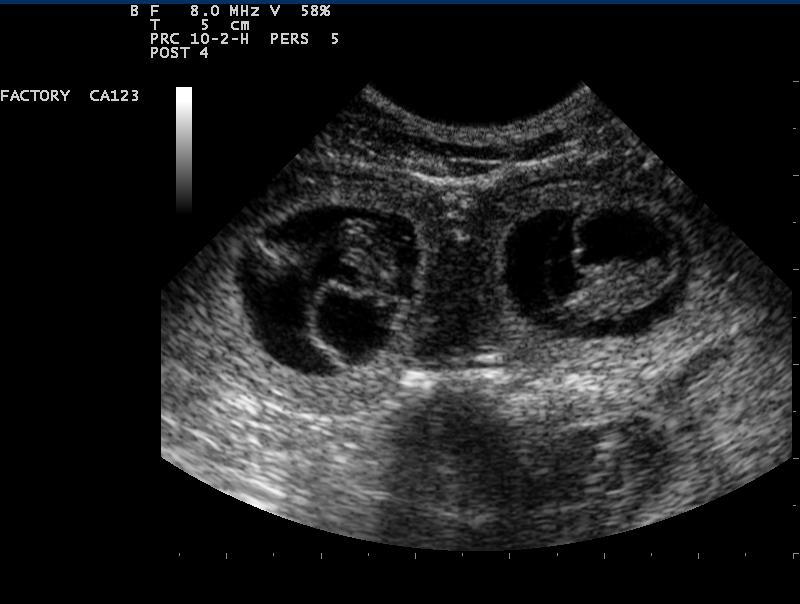

Auch in der Veterinärmedizin wird das schonende Verfahren der Ultraschalldiagnostik zunehmend eingesetzt. Wir verwenden es im Bereich der Abdominal- und Trächtigkeitsdiagnostik .